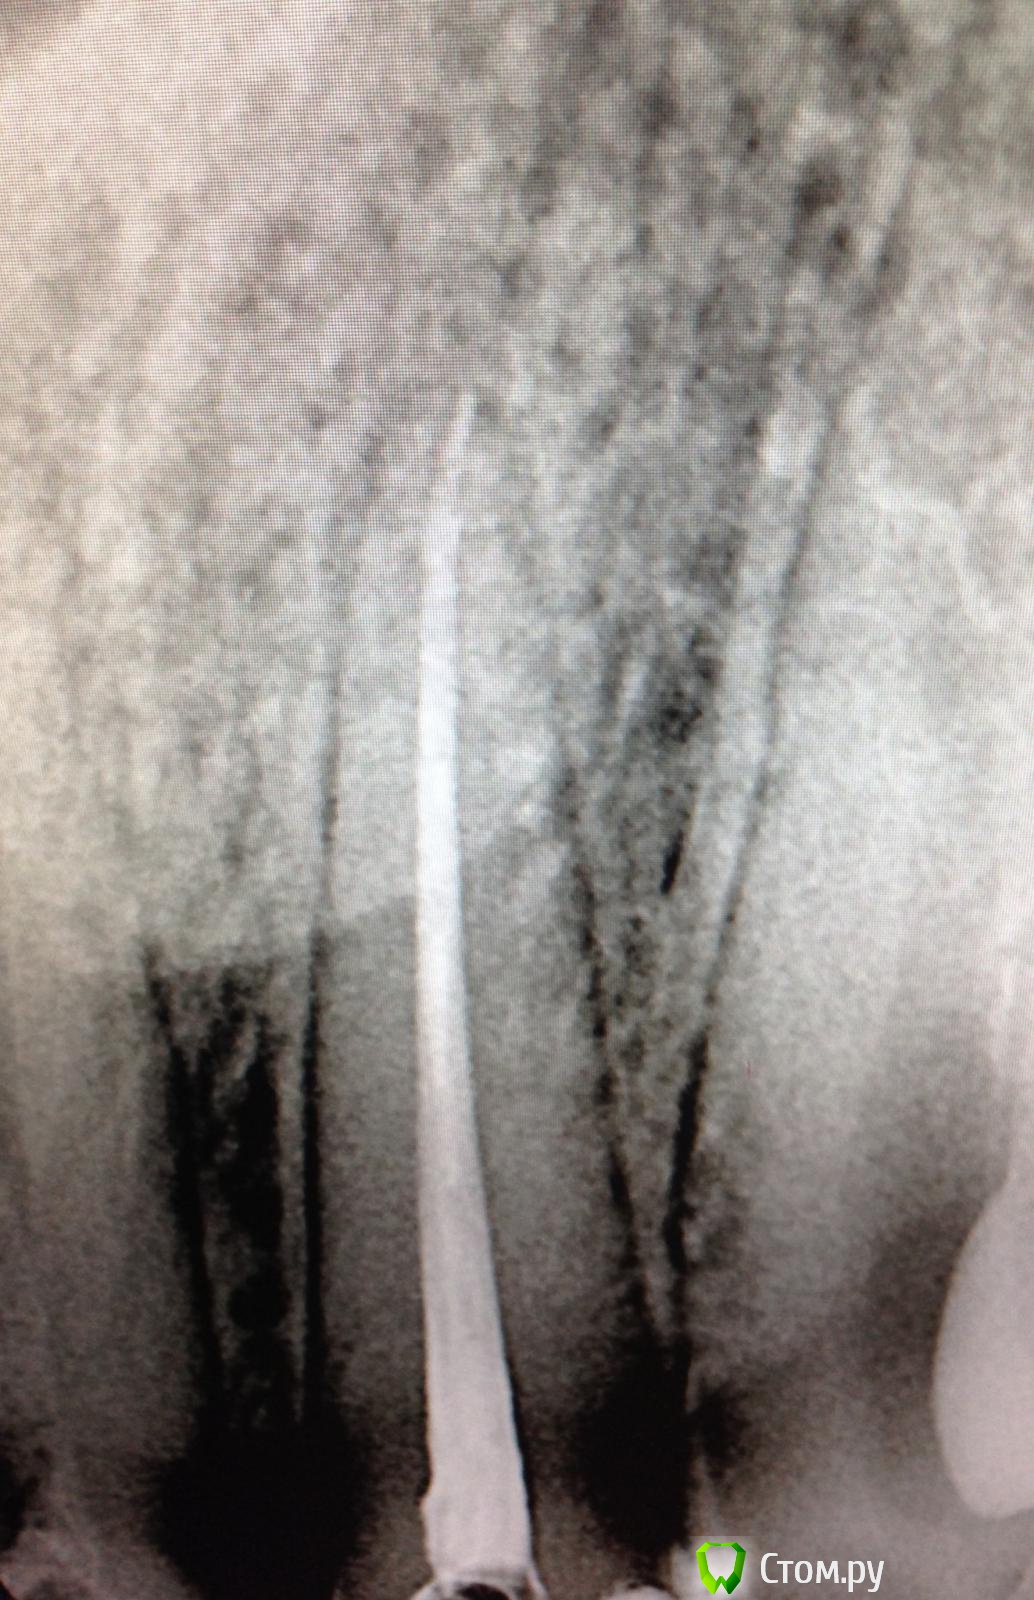

SSTi Опубликовано 19 сентября, 2014 Автор Поделиться Опубликовано 19 сентября, 2014 Новая кривулина. Начало. Попросил доктор знакомый полечить...)Неделю боли на накусывание. Иррадиируют в левый висок. Зуб 27. Внешне все ок. Маааленькая точечка в фиссуре. Шестерки нет. Делаю снимокТааааак. Позвонил доктору, сказал , как я счастлив, и приступил. Преп. Коффер. Дистально на уровне десны. Небный дистальный бугор ушел. В полости небольшой склероз. Мб сразу прошелся. Вообще без проблем. Только при хрусте файлов я чуть вспотел в области крестца))) расширились до 30.04 и дальше ручками 35.02. Мб 2 пока не нашел. Сулькус раскрыл - но там глухо. Поищем в следующий раз. Дистальный сначала только до уровня , как на снимке, потом прошел. Тоже 30.04 и 35.02. Небный- последние 3-4 мм дались с трудом. Но прошли. До 35.04 и 40.02. Мылись, сушились, кальцифицировались. Времянка. Продолжение следует 3 Ссылка на комментарий